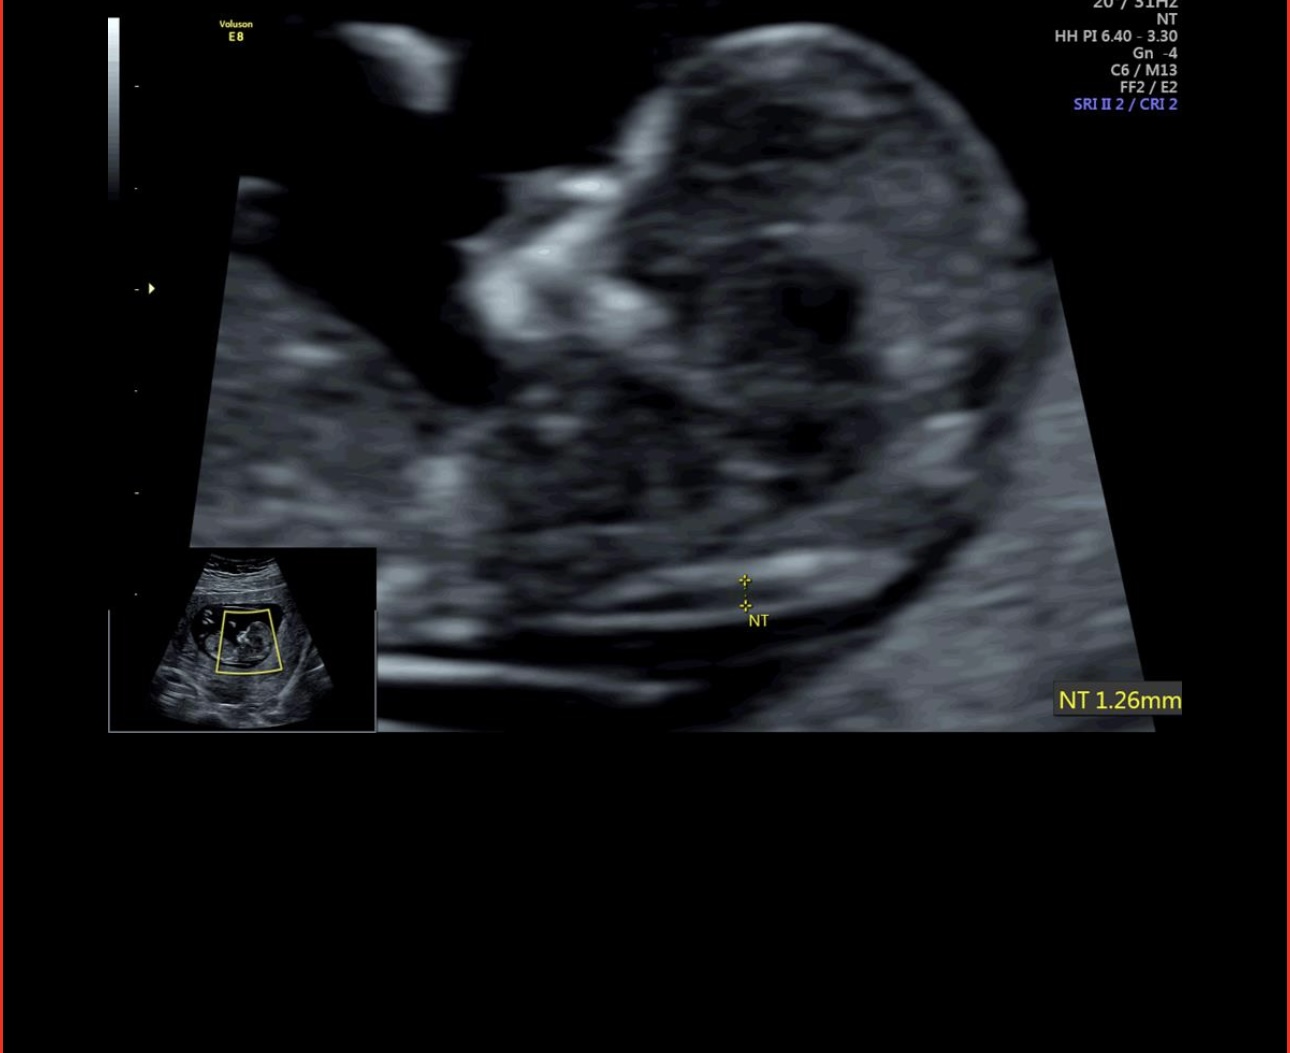

امروز رفتم انتی دادم خداروشکر همه چیز خوب بود

عکس های انتی رو الان میذارم ممنون میشم نظرتون رو بگید بهم